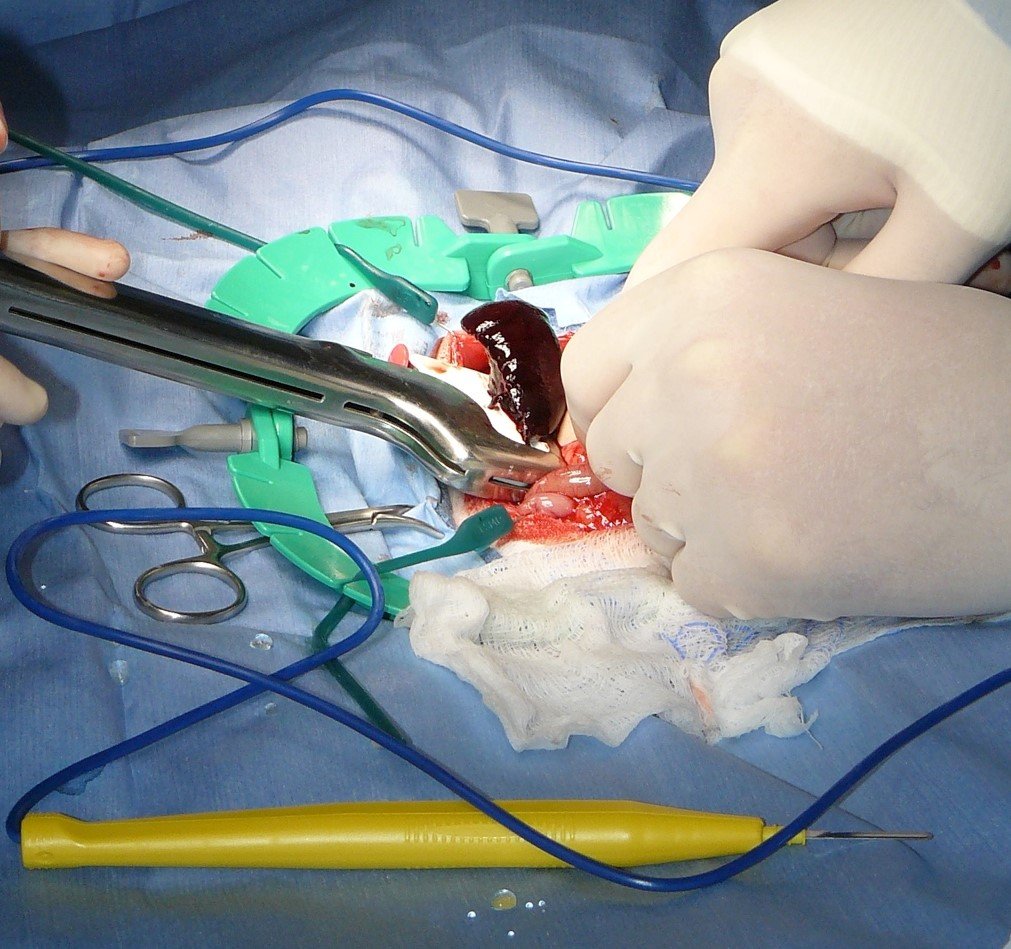

العلاج

- تدخل جراحي طارئ لاستئصال الفص الملتوي.

- يعتمد الإنذار على سرعة التشخيص والتدخل.

(عملية استئصال , لاحظ اللون الداكن جدًا لفص الكبد المستأصل لدى هذا المريض. لون الفص المصاب أغمق بكثير من فصوص الكبد الطبيعية.)